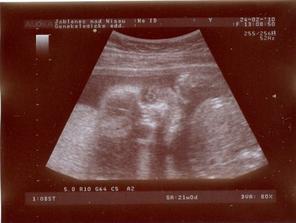

24.2.2010 - Velký utz!!! - ČEKÁME CHLAPEČKA - BUDE TO DAVÍDEK!!!!

Dle utz 21+3tt, vše jak má být, Davídek je naprosto zdravé miminko 🙂